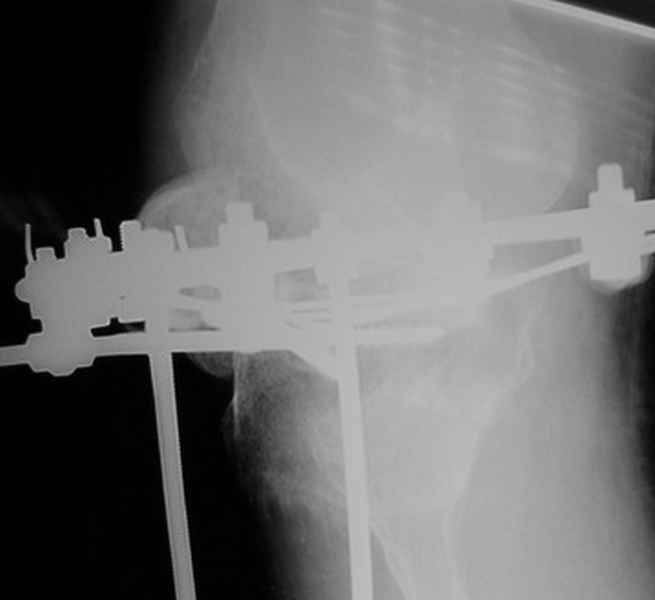

Пациент В. 53 лет, травма в феврале 2009. ДЗ. Открытый оскольчатый перелом нижней трети голени. При боли поступлении выполено ПХО, аппарат Илизарова. В последующем проводили ВХО, резекция костных отломков, укорочение 6 см, рана зажила. Была выполнена остеотомия большеберцовой кости в проксимальном отделе, резекция. Производилось тракция. На последних рентгенограммах выявлено, что одновременно с "выращиванием" регенерата произошло низведение надколенника на длину выращенного регенерата. Клинически: активное разгибание сохранено, объем движений в колене 180-110 градусов. Черными стрелками обозначен верхний край надколенника с одной и с другой стороны. Красная стрелка обозначает пальпируемую связку надколенника. Причина - остеотомия выше места прикрепления связки надколенника. Вопрос: была ли у кого подобная ситуация? Что делать? При первом обдумывании приходит решение: отсечение места прикрепления связки надколенника с костным блоком, перемещение на "правильное" место, укорочение сухожилия четырехглавой мышцы.

По снимкам - плотность регенерата хорошая, сложностей с фиксацией в него костного "основания" быть не должно.